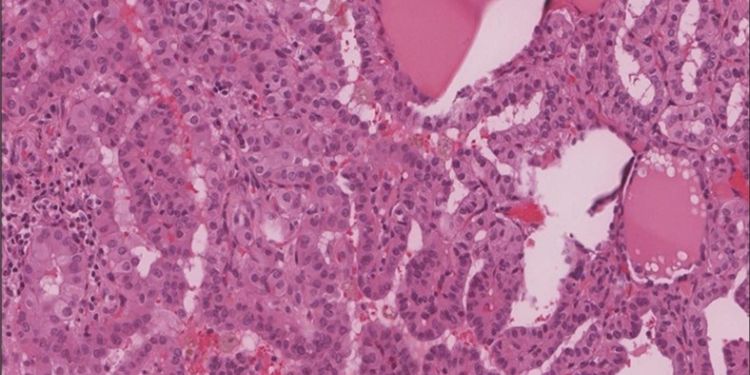

Primary Leiomyosarcoma of the Thyroid; a Case Report and a Review of Recent Literature

DOI: 10.14302/issn.2574-4496.jtc-23-4674

Published on 24 Aug 2023

Read the full article